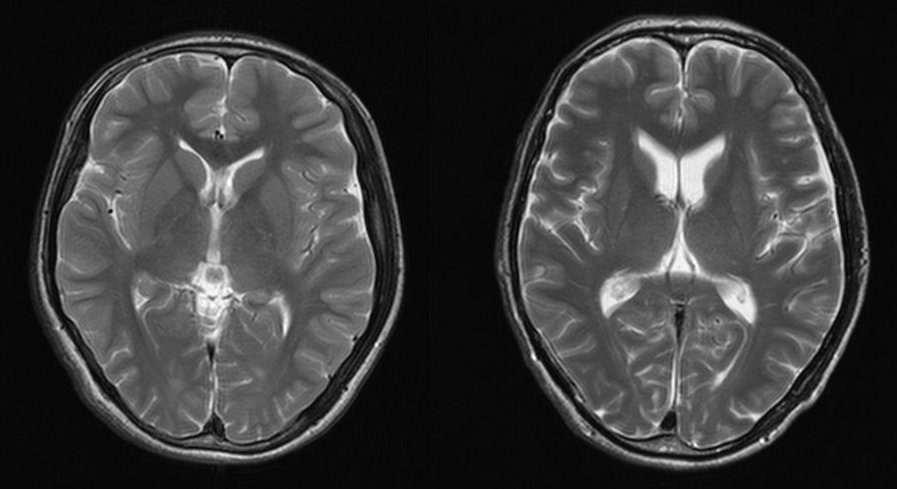

伊澤 心臓震盪はタイミングで起きる、胸だけではなく腹や背部でも起きる。また子供の脳は隙間が無く、出血したらすぐに危険な状態になるリスクがある。また子供の脳は血管が細い為、外傷に弱く出血のリスクが高い。などなどが特に印象に残りました。